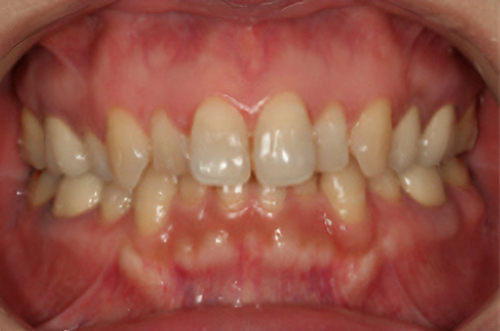

歯の形、歯並び、歯肉ラインが整う美しい口元

大掛かりな歯ぐきの手術や装置を使った矯正治療を行わずに、たった2回で歯並びをきれいに整えることができます。

術前

術後

BTAテクニック® とは

従来のセラミックで治すオールセラミックという被せ物や、セラミックを張り付けるラミネートべニアという方法に、歯科医師と歯科技工士の双方の手法と技法を癒合させることで、可能とした 歯ぐきのラインを2回の来院で、綺麗に仕上げ、歯の見た目も審美的に出来るテクニックのことである。

BTAテクニック® 以外の一般的な治療で歯ぐきのラインを整えるには、歯ぐきを切り、骨を削る手術をすれば可能ですが、歯ぐきの治りに数か月の期間が必要です。もしくは、矯正治療によって、歯並びを改善する方法、もしくは神経を抜いて、被せ物をするしかありません。

BTAテクニック® を用いると、歯ぐきや骨への手術が必要ない為に、治療期間が短縮でき、2回の来院で完了できるメリットがある。 また、この方法を用いることで、年々歯ぐきが下がって見た目が悪くなるということが起きにくくなる。歯周ポケットと言われる溝が浅くなり、歯ブラシが容易になる。などの利点が挙げられる特殊なテクニックである。

また、救歯BTAセラミックは、BTAテクニック®が持つ成功する理由(*)から、深い位置まで虫歯が進行してしまって歯を抜かないとならない歯に応用する事で、抜かずに治療することが出来る場合がある。

症例によっては、BTAテクニック® , 救歯セラミックが適応出来ない場合があります。 また、この方法を用いることで必ず歯が残せるという治療方法ではありません。

価格

> 1歯 165,000円